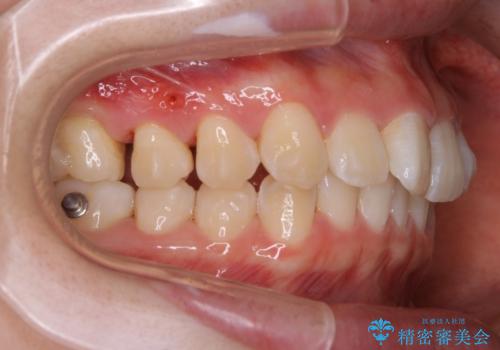

非抜歯矯正

マウスピースとマイクロインプラントを組み合わせることで、抜歯をしなくても歯並びを治すためのスペースを作ることができます。奥歯から順に移動させていくので前歯に変化が出るまでには時間がかかりますが、どの分健康な歯を抜歯することなく理想的な歯並びを手に入れることができます。